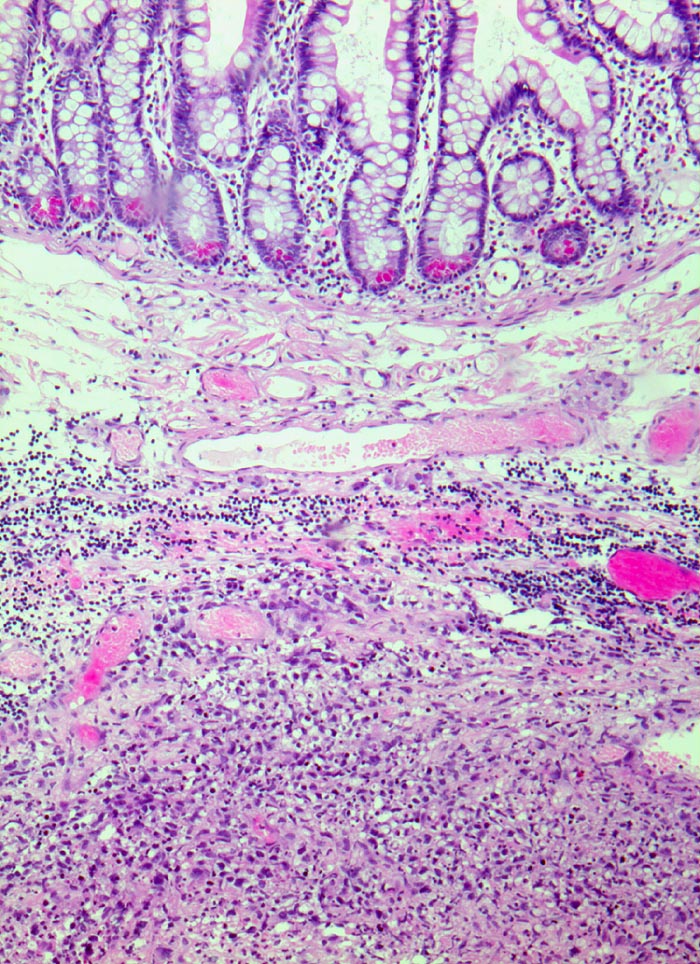

PathoPic ID 3460 - extranodales diffuses grosszelliges B-Zell Lymphom (WHO)

extranodales diffuses grosszelliges B-Zell Lymphom (WHO)

Ileum

Grosszelliges Lymphominfiltrat in der Submukosa.

Immunhistochemie: CD20 positiv, CD3 und CD30 negativ, CD117 negativ

Akute Peritonitis bei Darmperforation